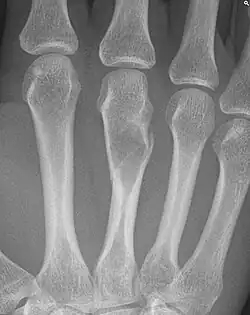

Pathologische fractuur

Een pathologische fractuur wordt gedefinieerd als een fractuur die ontstaat door een al bestaande verzwakking van het betreffende bot, door een lokale verzwakking of een systemische ziekte. Een dergelijke fractuur kan spontaan of na een gering trauma optreden. De meest voorkomende oorzaken zijn tumoren in het bot (uitzaaiingen van een kwaadaardig gezwel ofwel botmetastasen, of primaire bottumoren (osteosarcoom, Ewing-sarcoom of chondrosarcoom) en osteoporose.